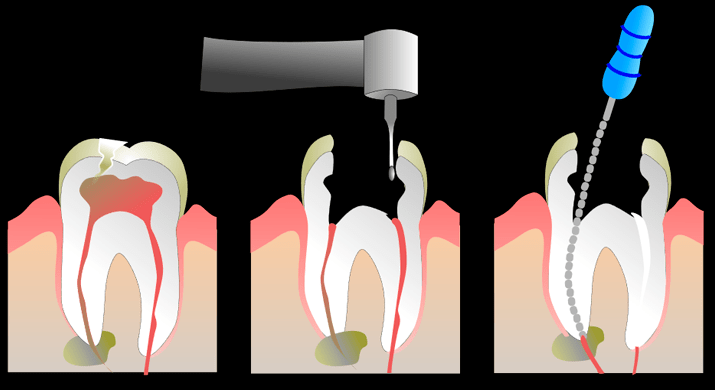

Pulpotomías: Tratamiento parcial de la pulpa dental en dientes de leche, donde se retira únicamente la parte afectada y se sella con un agente biocompatible para conservar la función y evitar extracción.

Pulpectomías: Endodoncia completa en dientes temporales muy dañados, que consiste en limpiar y desinfectar todo el conducto radicular, luego rellenarlo con material reabsorvible hasta la caída natural del diente.